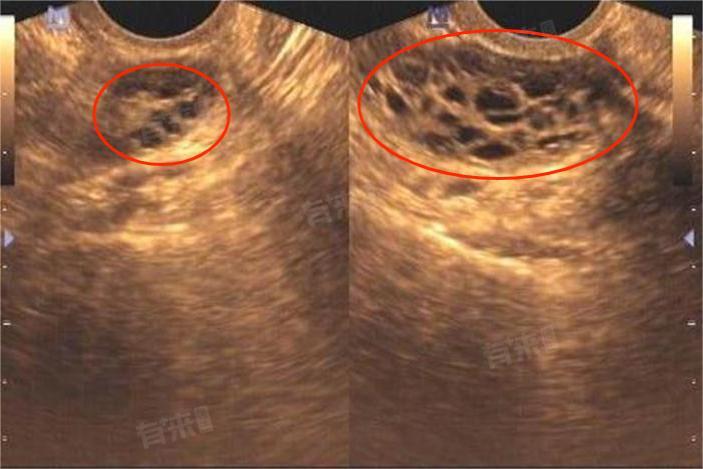

双卵巢多囊样改变是一种在妇科超声检查中观察到的卵巢形态学改变。正常情况下,卵巢在超声图像中呈现出一定的形态和结构,有规律地分布着不同发育阶段的卵泡。然而,当出现双卵巢多囊样改变时,超声检查会发现双侧卵巢体积增大,且卵巢内可见多个直径在2-9毫米的小卵泡。